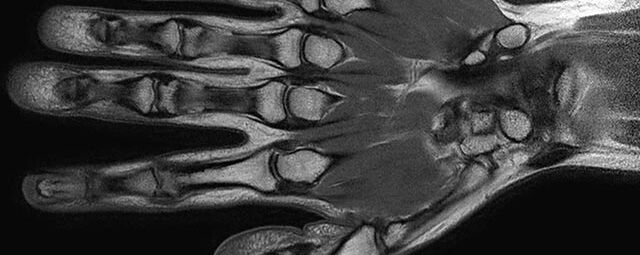

- Beurteilung von Knochen, Bändern und anderen Weichteilstrukturen der Gelenke nach Unfall.

- Arthrosediagnostik (Knorpelschaden)

- Impingement-Symptomatik

- Ursachenklärung bei wiederholter spontaner Gelenkluxation

- Ausbreitungsdiagnostik bei Gelenkentzündung, z.B. im Rahmen von rheumatischen Grunderkrankungen

- MR-Arthrographie – nach örtlicher Betäubung und gründlicher Desinfektion der Haut wird unter Lagekontrolle mit Röntgen-Durchleuchtung eine kleine Nadel in den Gelenkraum positoniert und darüber ein MR-taugliches Kontrastmittel in den Gelenkraum gespritzt. Danach wird die Nadel entfernt. Anschließend erfolgt die MRT des Gelenkes. Diese Methode stellt kleine anatomische Strukturen des Gelenkraumes verbessert dar, z.B. zur Therapieplanung vor Arthroskopie bei Sportverletzungen der Schulter oder Gelenkinstabilität.